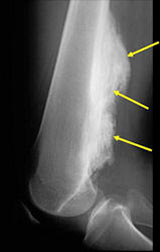

- Lobulated and ossified exophytic mass (cauliflower-like) adjacent to the cortex; attached to metaphyseal cortex via a broad base

- Large tumors encircle the bone

- Appears to have broad attachment to underlying cortex with a cleft between exophytic base and cortex at periphery. This is referred to as a “String Sign” (cleft is often only identifiable on CT scan)

- High grade or defifferentiated areas may appear as large radiolucent areas/mass adjacent to radiodense areas